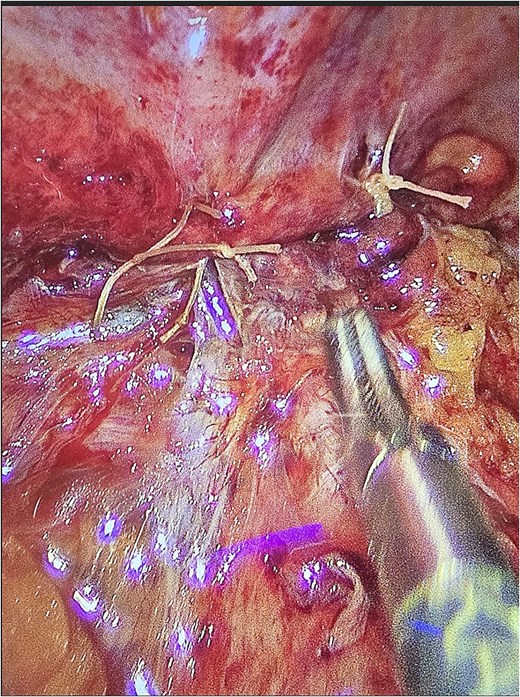

The patient underwent laparoscopic appendectomy with laparoscopic enterolysis. The appendix appeared inflamed, dilated, and gangrenous, with a perforation located 2 cm from the base. Notably, the appendix was not in a retrocecal position as initially suspected but was found to be herniating through a defect in the iliacus muscle (Fig. 3). The appendix was circumferentially freed from the hernia defect, which was identified as tracking cephalad between the iliacus muscle and the iliac bone. The hernia defect measured 2.5 cm and was primarily closed using two figure-of-eight 2–0 Vicryl sutures, leaving a small inferior opening to allow for drainage (Fig. 4). A 19 Fr Blake drain was placed in the right lower quadrant and paracolic gutter.

Iliacus hernia defect closed primarily after appendix was removed.